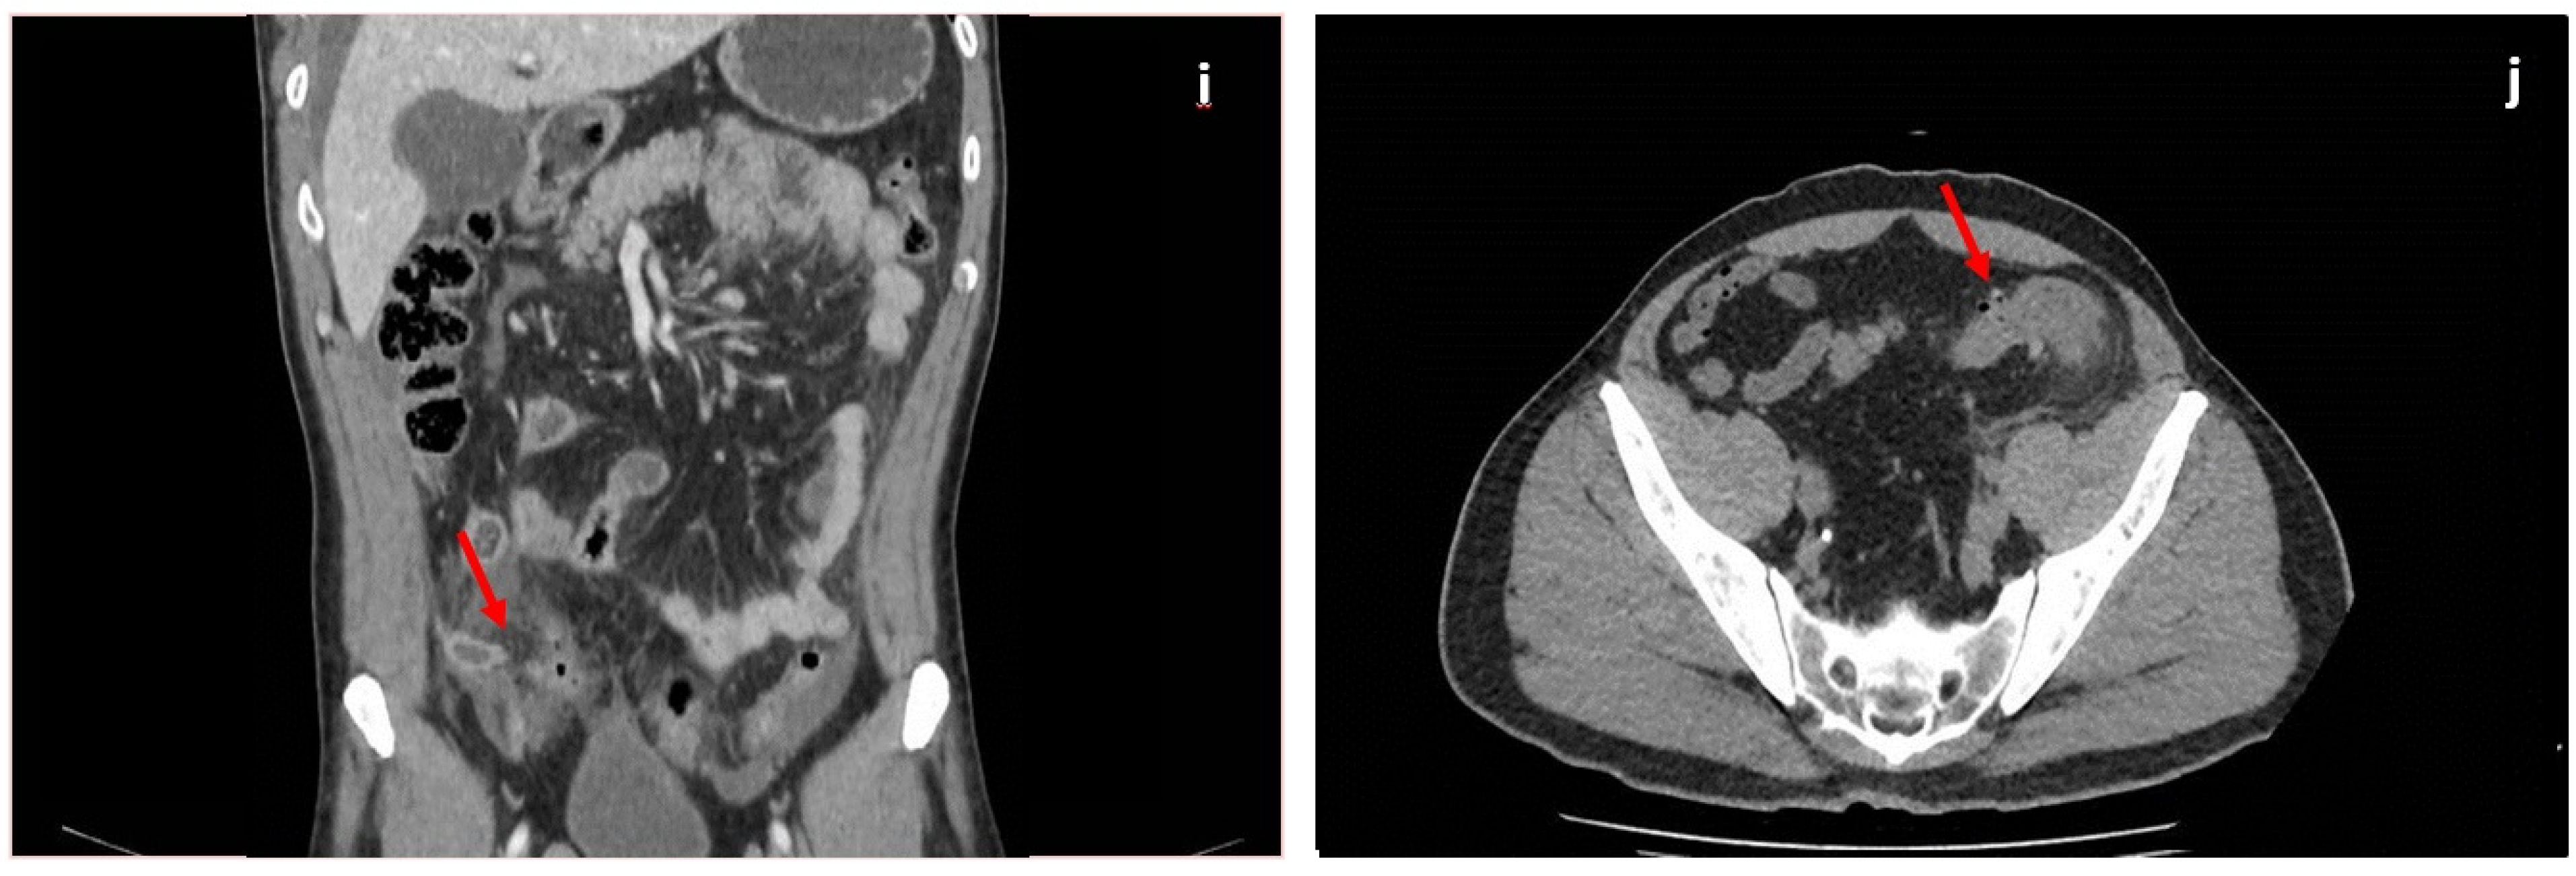

5.1. Acute Appendicitis